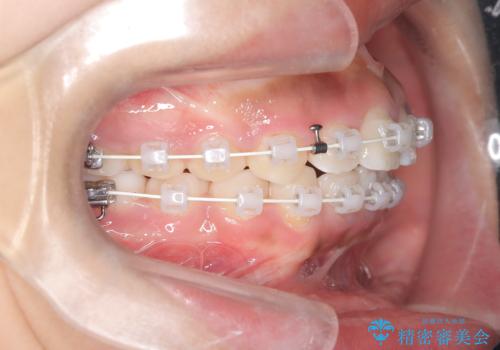

- 患者様は前歯の突出を主訴に来院されました。診査の結果、上顎の前歯が前方に傾斜しており、口元がやや突出して見える状態でした。一般的にこのようなケースでは抜歯矯正が選択肢となりますが、**患者様が抜歯を希望されなかったため、非抜歯での遠心移動(奥へ動かす治療)を計画しました。そのため、リンガルアーチ(歯の裏側に装着する装置)とTAD(歯科矯正用アンカースクリュー)**を併用し、上顎の歯を後方へ移動させながら噛み合わせを整える方法を選択しました。

まず、上顎にリンガルアーチを装着し、歯列の幅を適正に維持しながら遠心移動をサポート。さらに、**TAD(矯正用アンカースクリュー)**を利用することで、奥歯を固定源とせずに前歯だけを後方へ移動させることが可能になりました。これにより、抜歯をせずに前歯の突出を抑え、バランスの取れた口元へと改善。治療後、患者様からは「抜歯せずに理想の仕上がりになり、大満足」とのお声をいただきました。